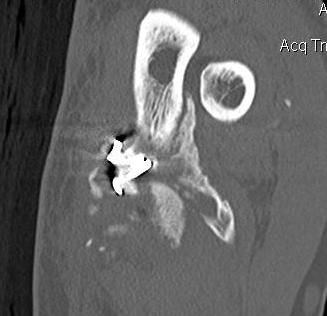

CT

Define anatomical location of the HO prior to surgical excision

- 56 elbows with post fracture HO

- 3D dimensional CT scans

- medial capsule 93%, lateral capsule 80%

- medial supracondylar 57%

- lateral supracondylar, radial head ulnar region 50%